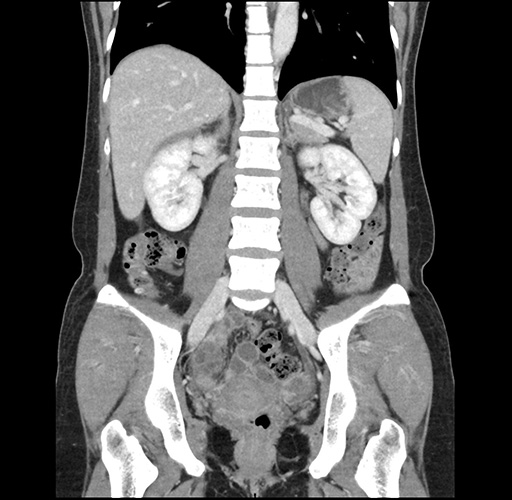

Imaging Analysis

Look through the patient's CT scan to identify any areas of concern for the necessary procedure.

Based on your CT findings, which issue(s) would give reason for "planned slowing down moment(s)" in this case?

Considering a standard left lateral sectionectomy procedure, what step(s) of the operation would you do differently in this case ?